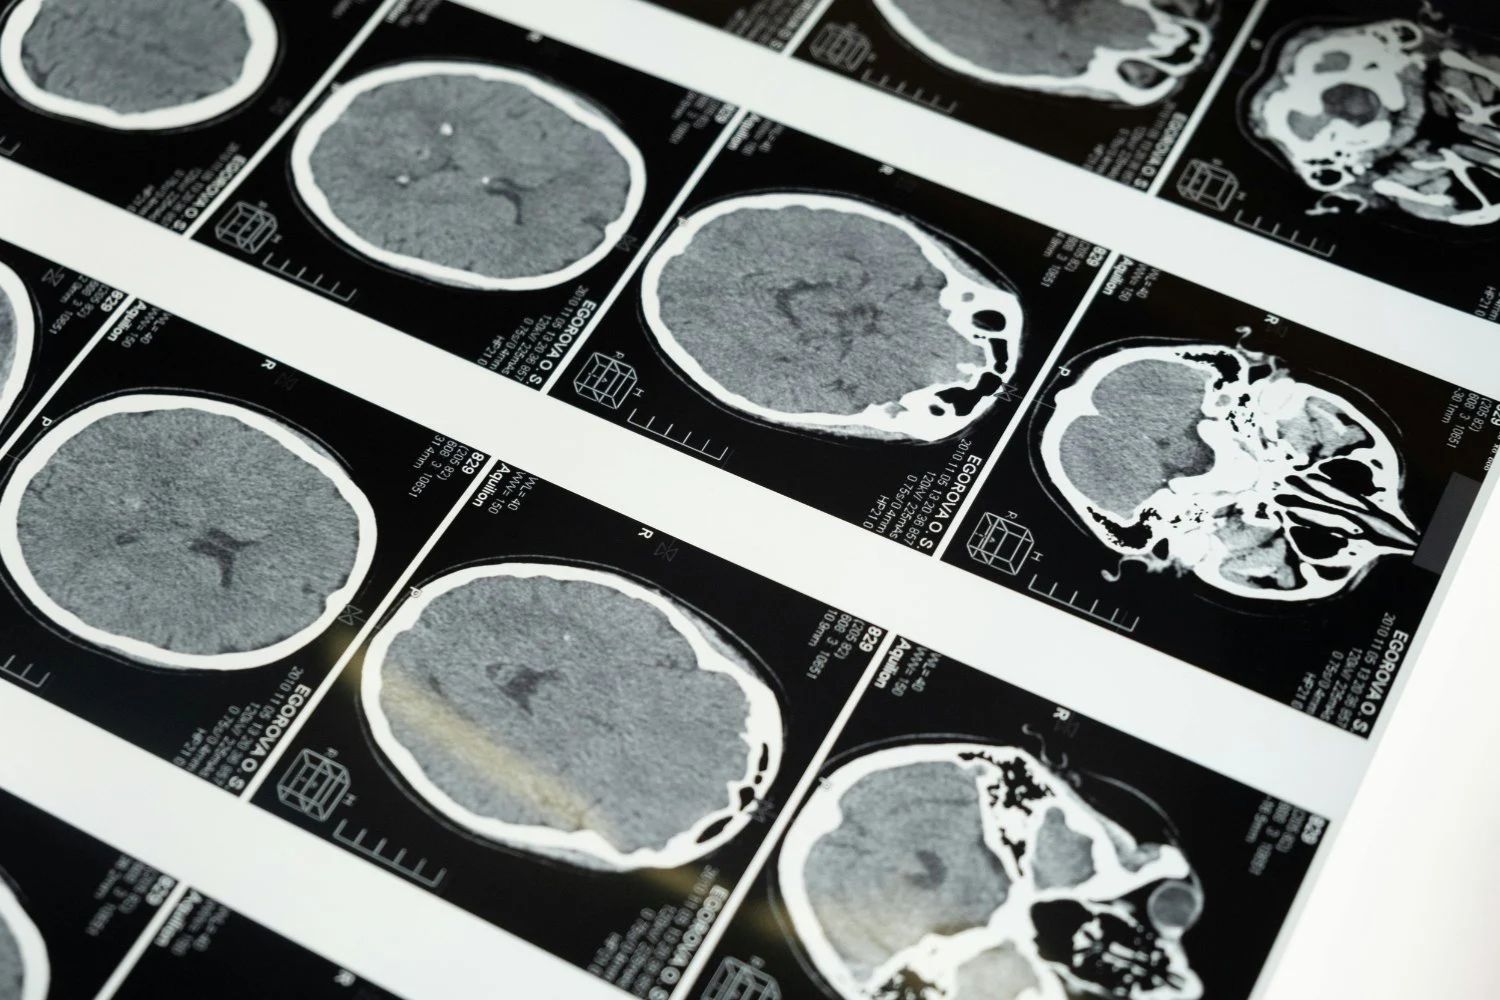

Julie hatte bereits zuvor einen Brustkrebs überstanden. Nach einer CT-Untersuchung fanden die Ärzte jedoch zwei inoperable Tumore. Ihr wurde erklärt, dass eine Chemotherapie nicht möglich sei und dass sie nur monatliche Injektionen sowie Kontrollen durch MRT und CT erhalten würde.